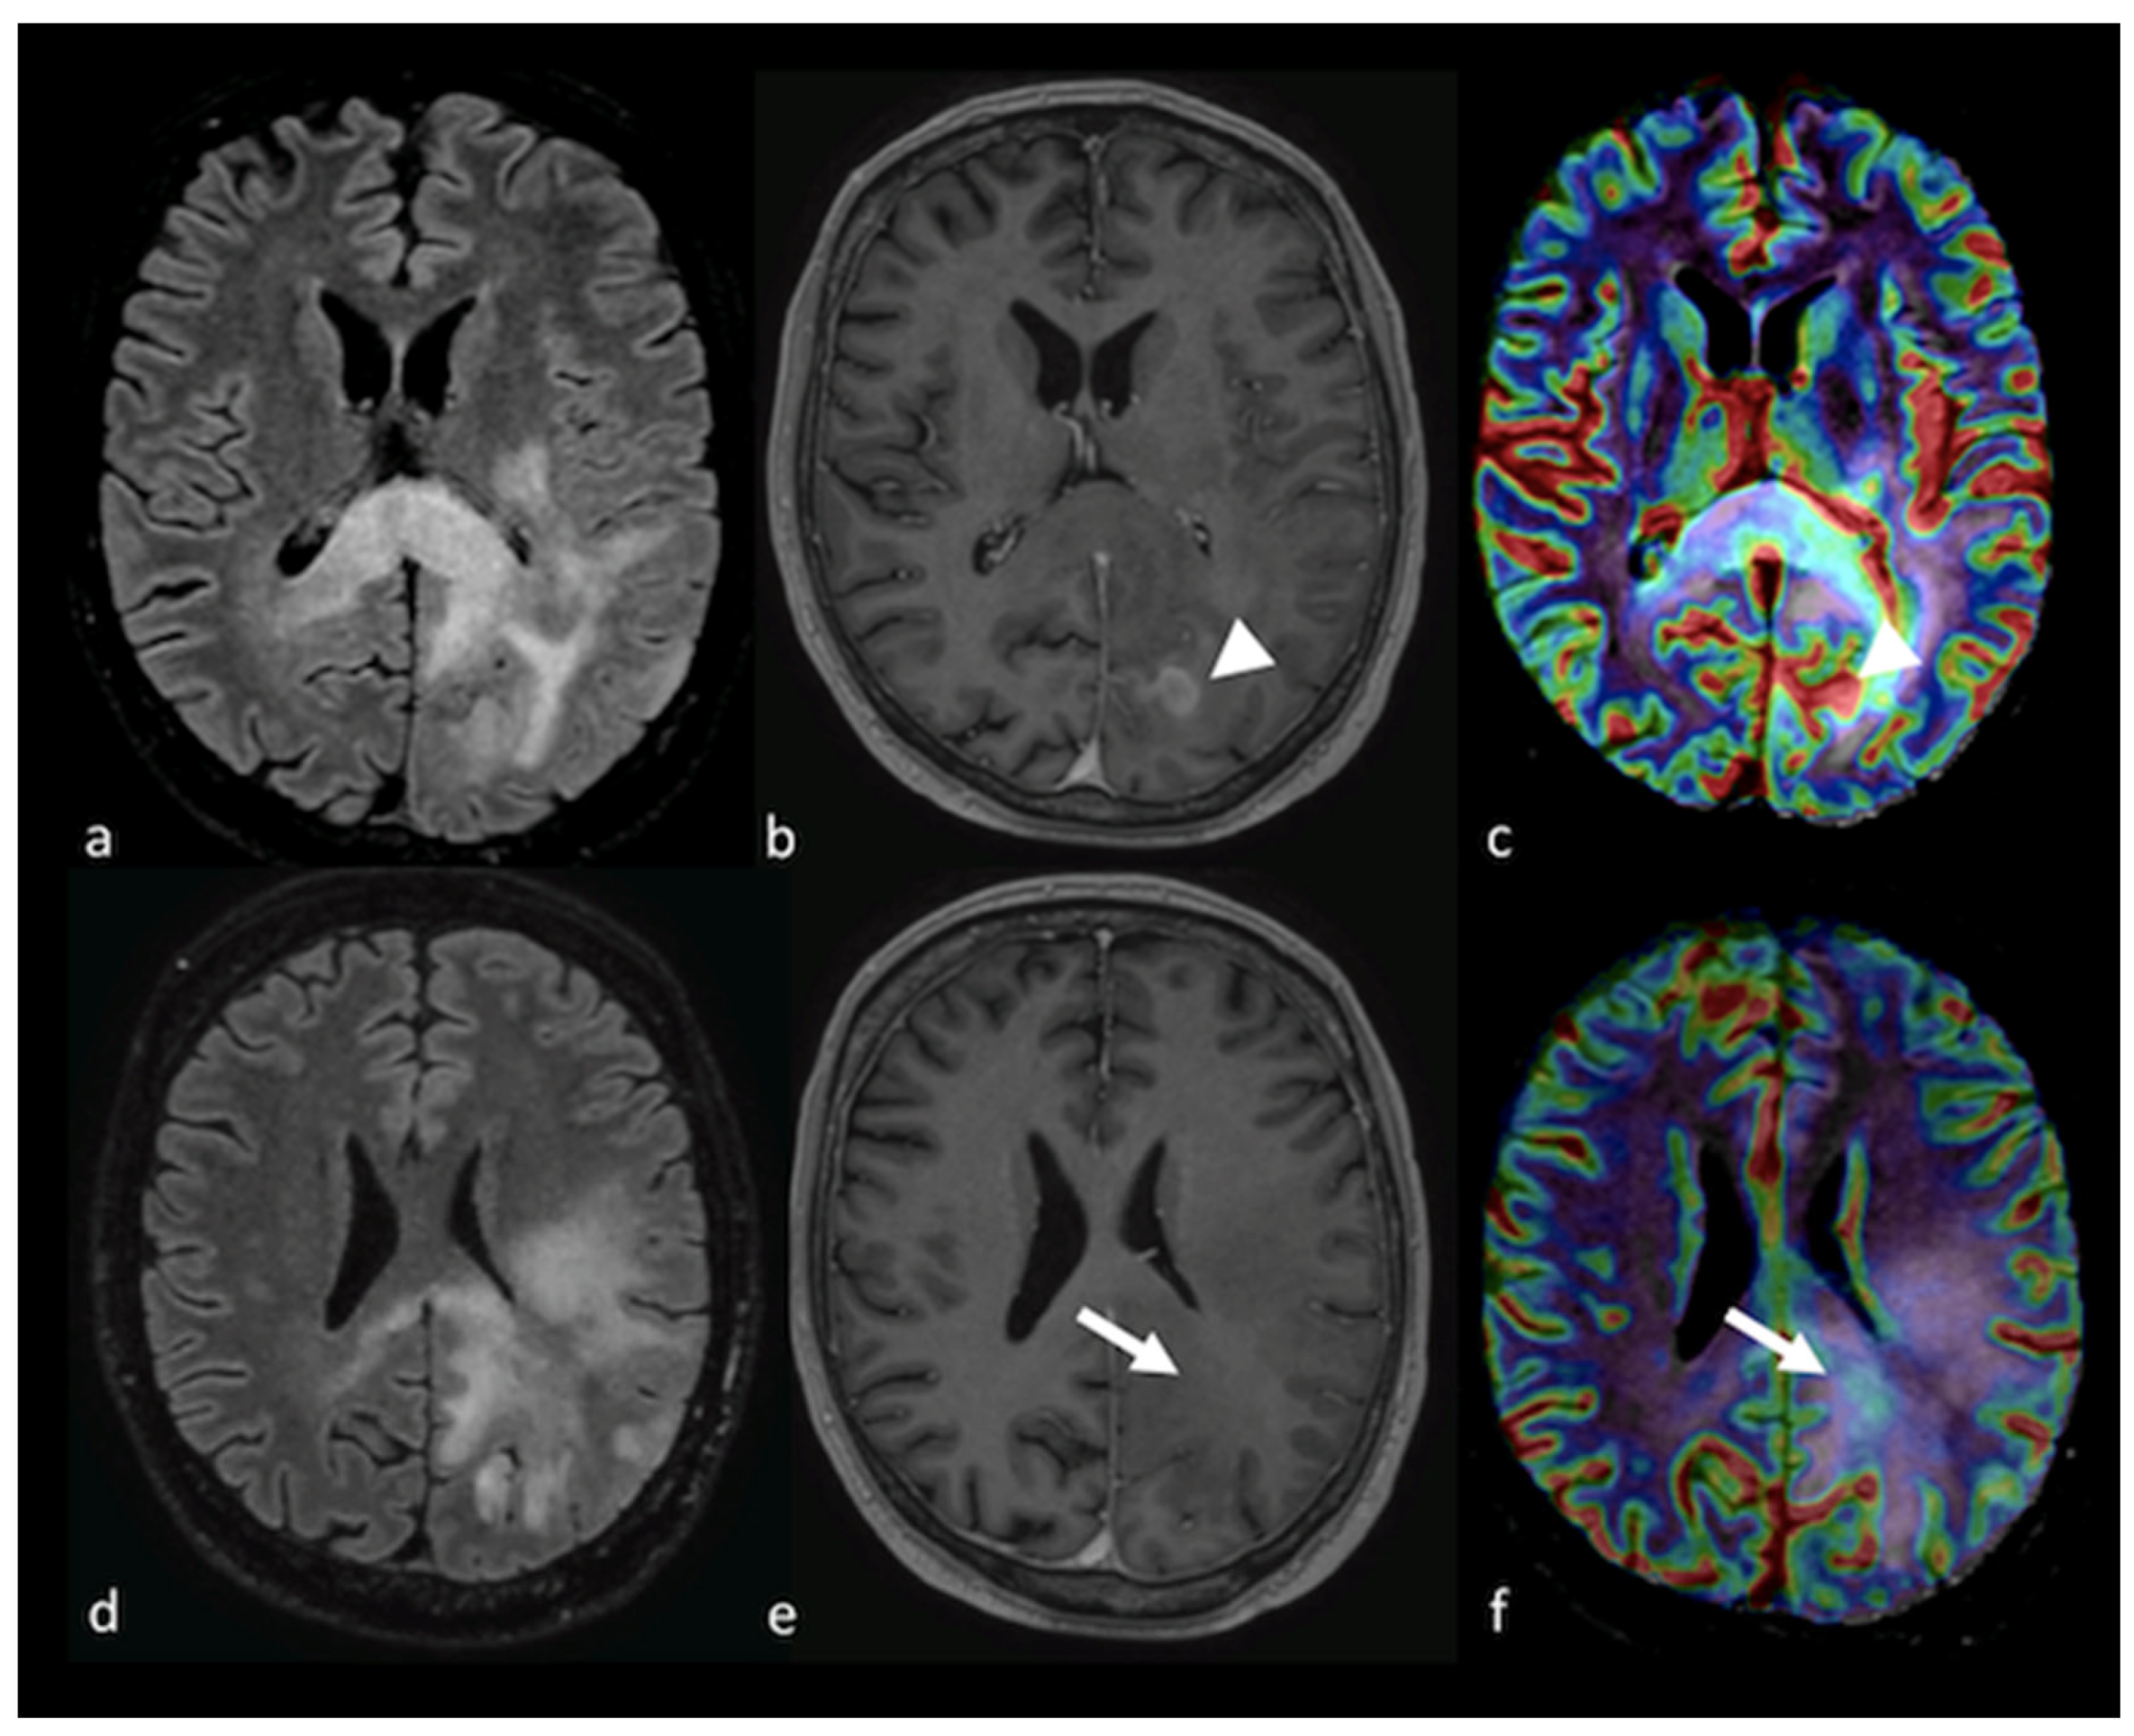

3.3.1. Dynamic Susceptibility Contrast-Enhanced Perfusion

- Neska-Matuszewska, M.; Bladowska, J.; Sasiadek, M.; Zimny, A. Differentiation of glioblastoma multiforme, metastases and primary central nervous system lymphomas using multiparametric perfusion and diffusion MR imaging of a tumor core and a peritumoral zone-Searching for a practical approach. PLoS ONE 2018, 13, e0191341. [Google Scholar] [CrossRef]

- Kickingereder, P.; Wiestler, B.; Sahm, F.; Heiland, S.; Roethke, M.; Schlemmer, H.P.; Wick, W.; Bendszus, M.; Radbruch, A. Primary central nervous system lymphoma and atypical glioblastoma: Multiparametric differentiation by using diffusion-, perfusion-, and susceptibility-weighted MR imaging. Radiology 2014, 272, 843–850. [Google Scholar] [CrossRef]

- Ma, J.H.; Kim, H.S.; Rim, N.J.; Kim, S.H.; Cho, K.G. Differentiation among glioblastoma multiforme, solitary metastatic tumor, and lymphoma using whole-tumor histogram analysis of the normalized cerebral blood volume in enhancing and perienhancing lesions. AJNR Am. J. Neuroradiol. 2010, 31, 1699–1706. [Google Scholar] [CrossRef]